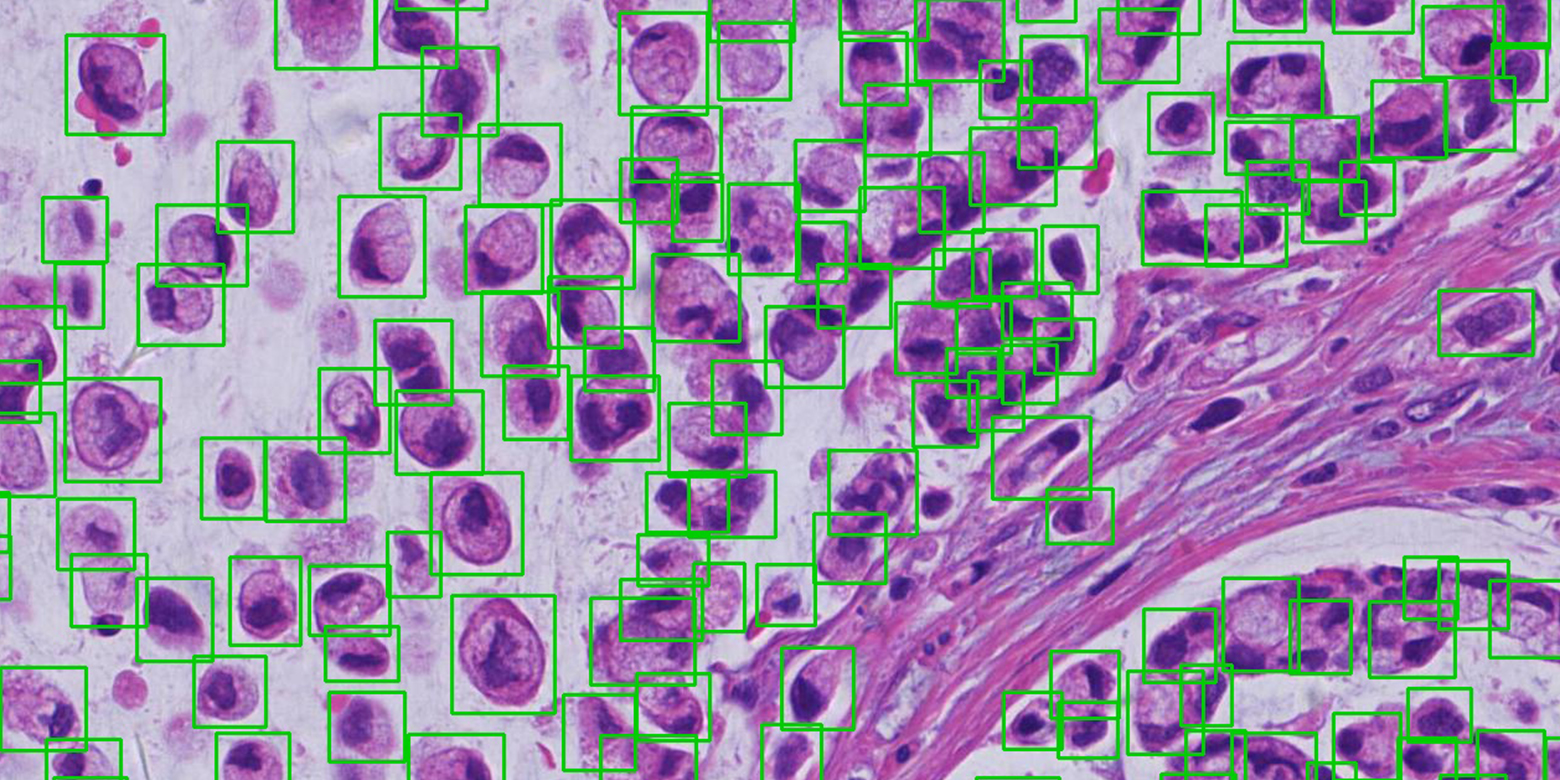

病灶/部位檢測與定位

運用領先的計算機視覺技術,對 CT、MRI、病理等等醫學圖像中的器官/部位進行快速的檢測和定位,例如 MRI/CT 影像的椎間盤及椎骨的定位、CT 影像的肺結節檢測與定位、病理圖像的細胞檢測與定位等等,方便醫生參考並提供更準確的診斷,提高診斷效率。

病灶/部位檢測與定位

運用領先的計算機視覺技術,對 CT、MRI、病理等等醫學圖像中的器官/部位進行快速的檢測和定位,例如 MRI/CT 影像的椎間盤及椎骨的定位、CT 影像的肺結節檢測與定位、病理圖像的細胞檢測與定位等等,方便醫生參考並提供更準確的診斷,提高診斷效率。